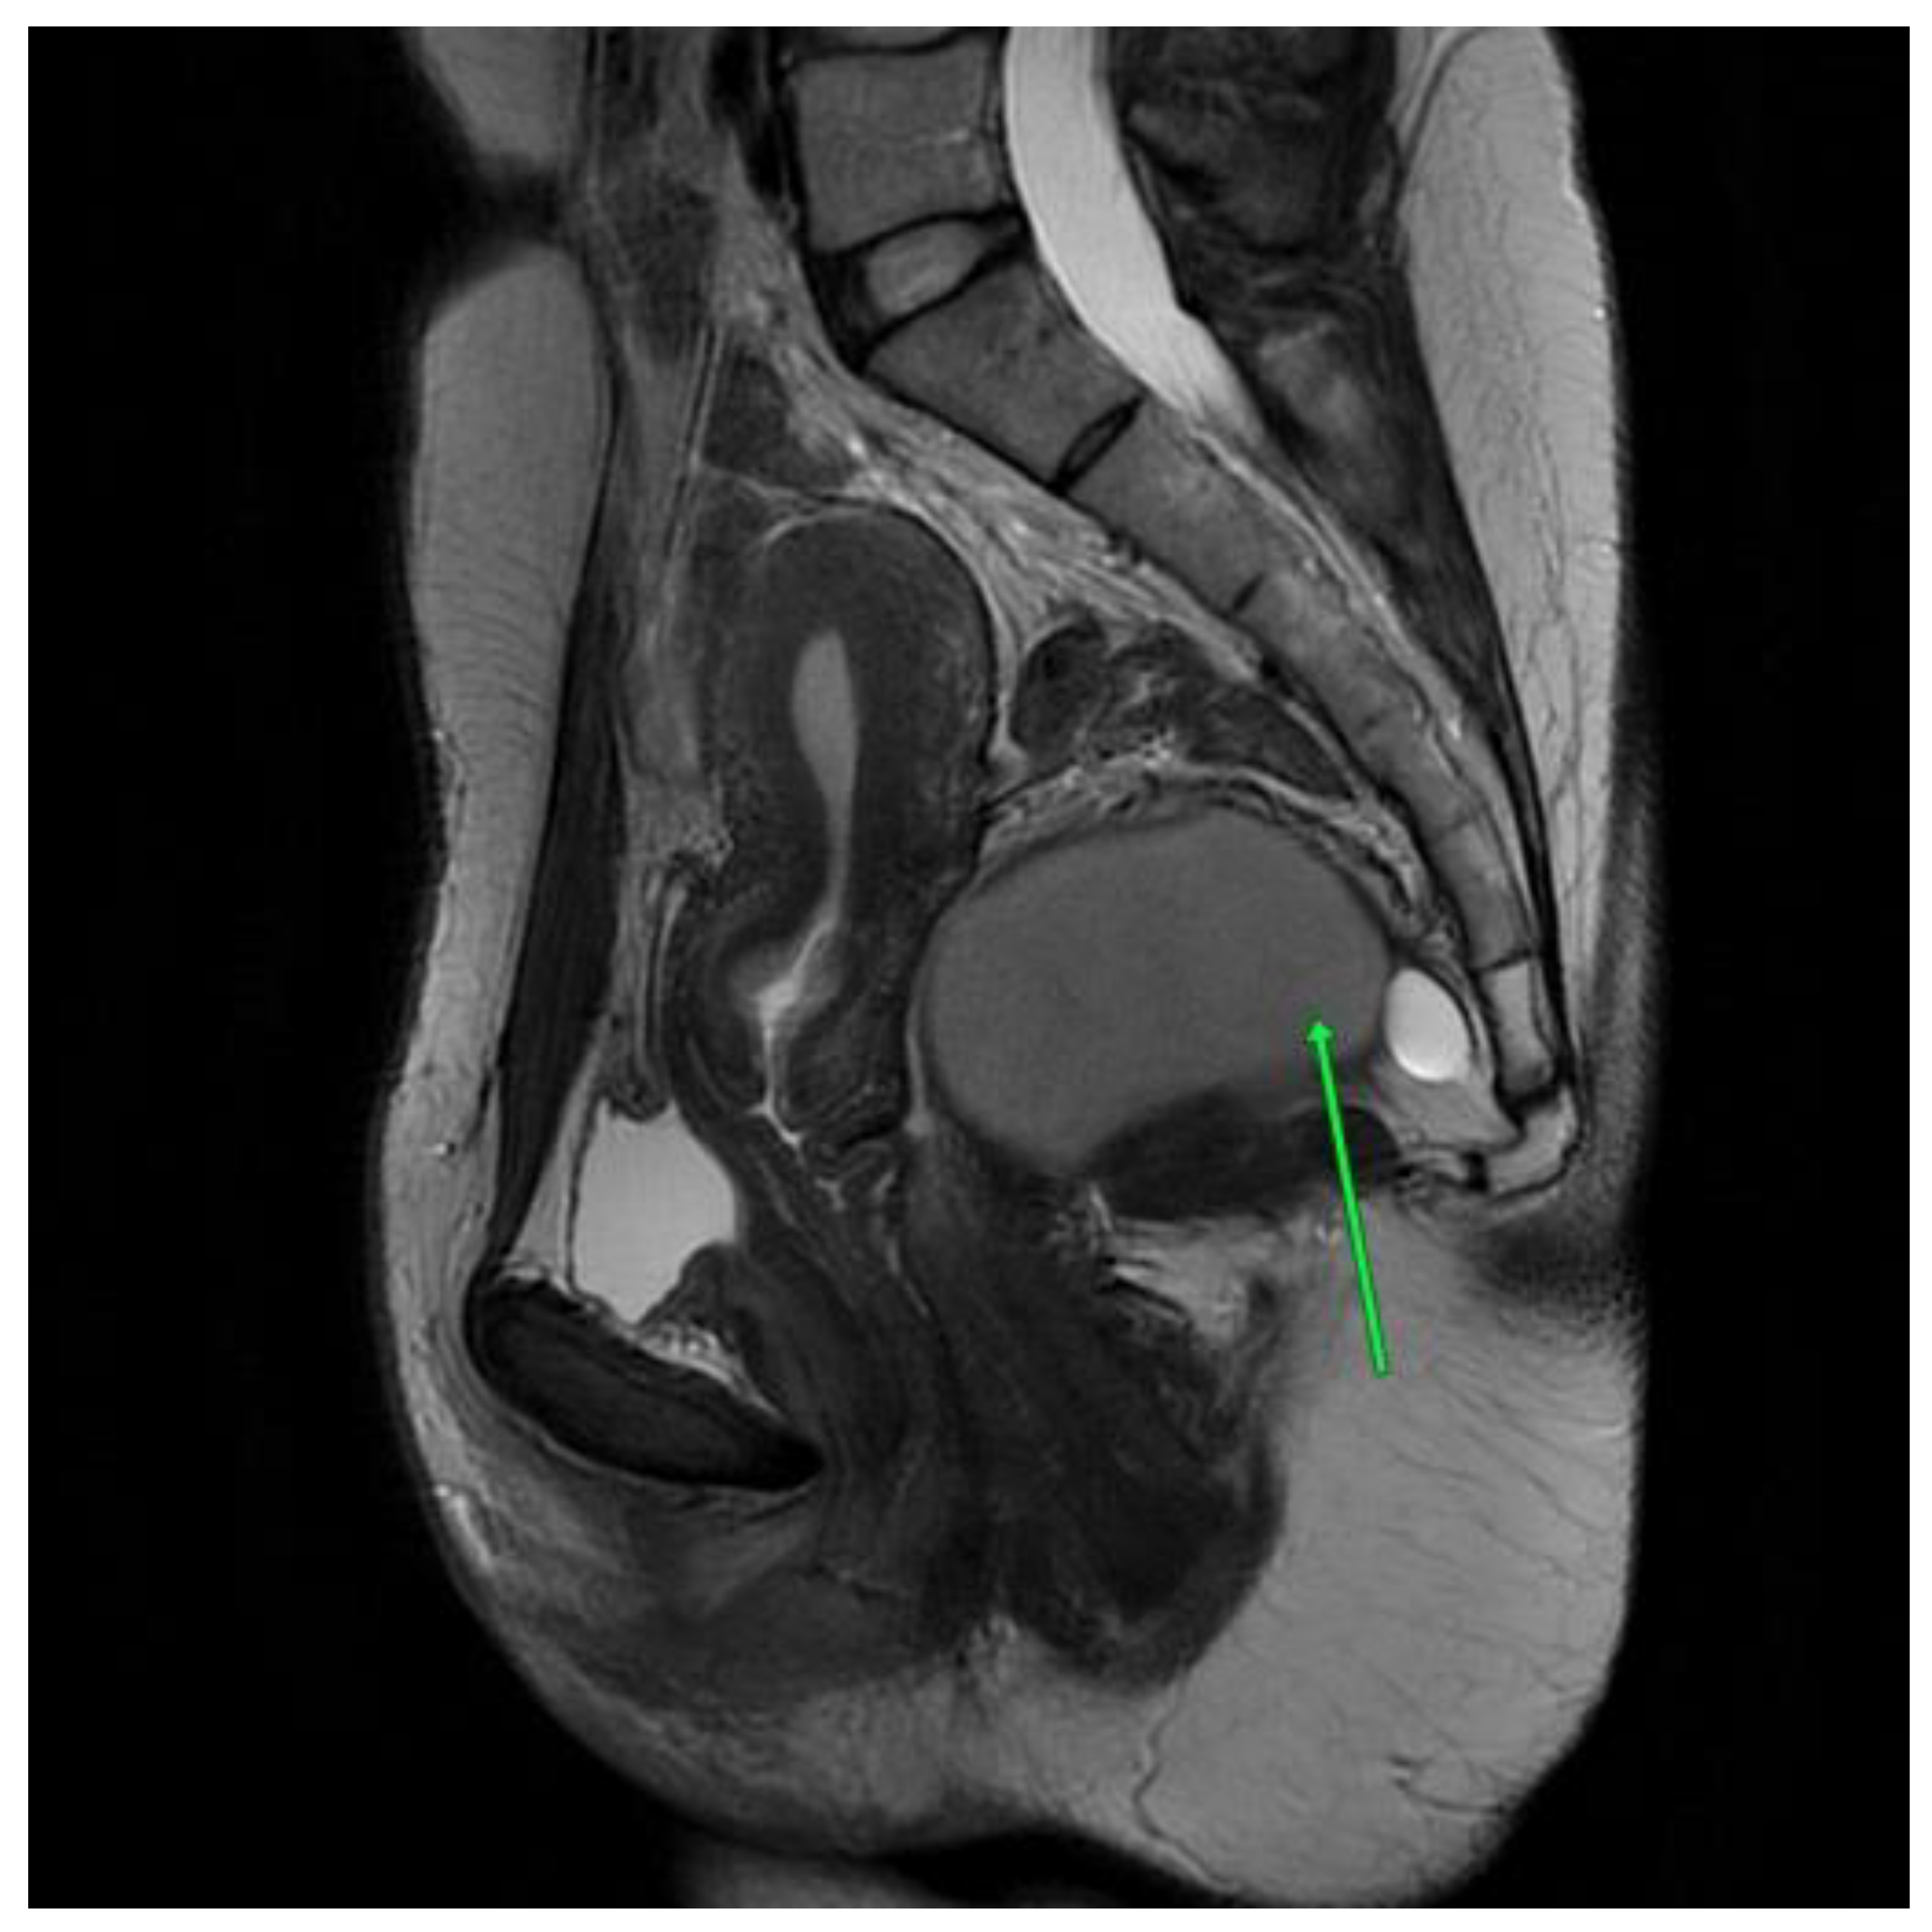

In the first MRI scan, eight months after the procedure, a small amount of fluid was visible in the operated area. Some small cystic, thin-walled structures were also visible, and will be monitored in future imaging [Figure 5].

Figure 5. Second patient MRI scan of the lesser pelvis eight months after the procedure.